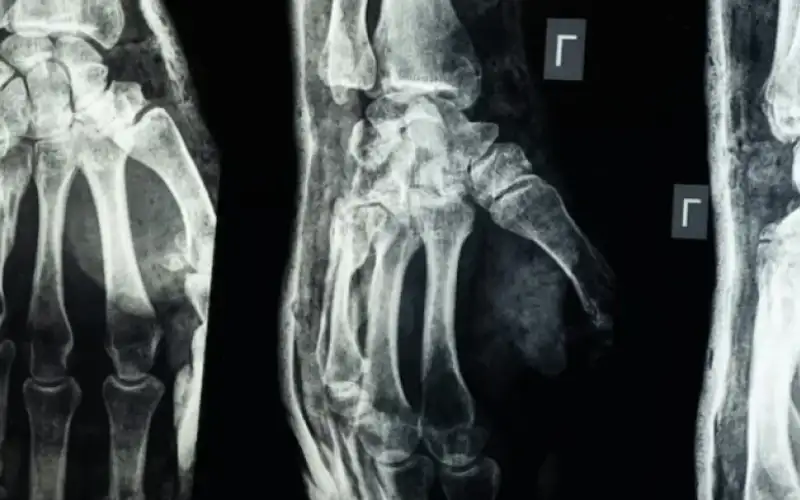

'غراء عظمي' .. ابتكار صيني لعلاج الكسور في 3 دقائق